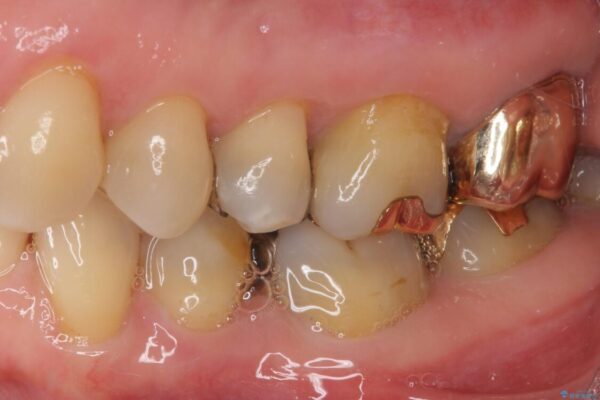

奥歯の銀歯が外れてしまったため、セラミック治療を希望された患者様です。

セラミックインレーによる修復治療を実施しました。

治療前

• 外れてしまった銀歯 セラミックインレーで自然な仕上がりに 治療前画像